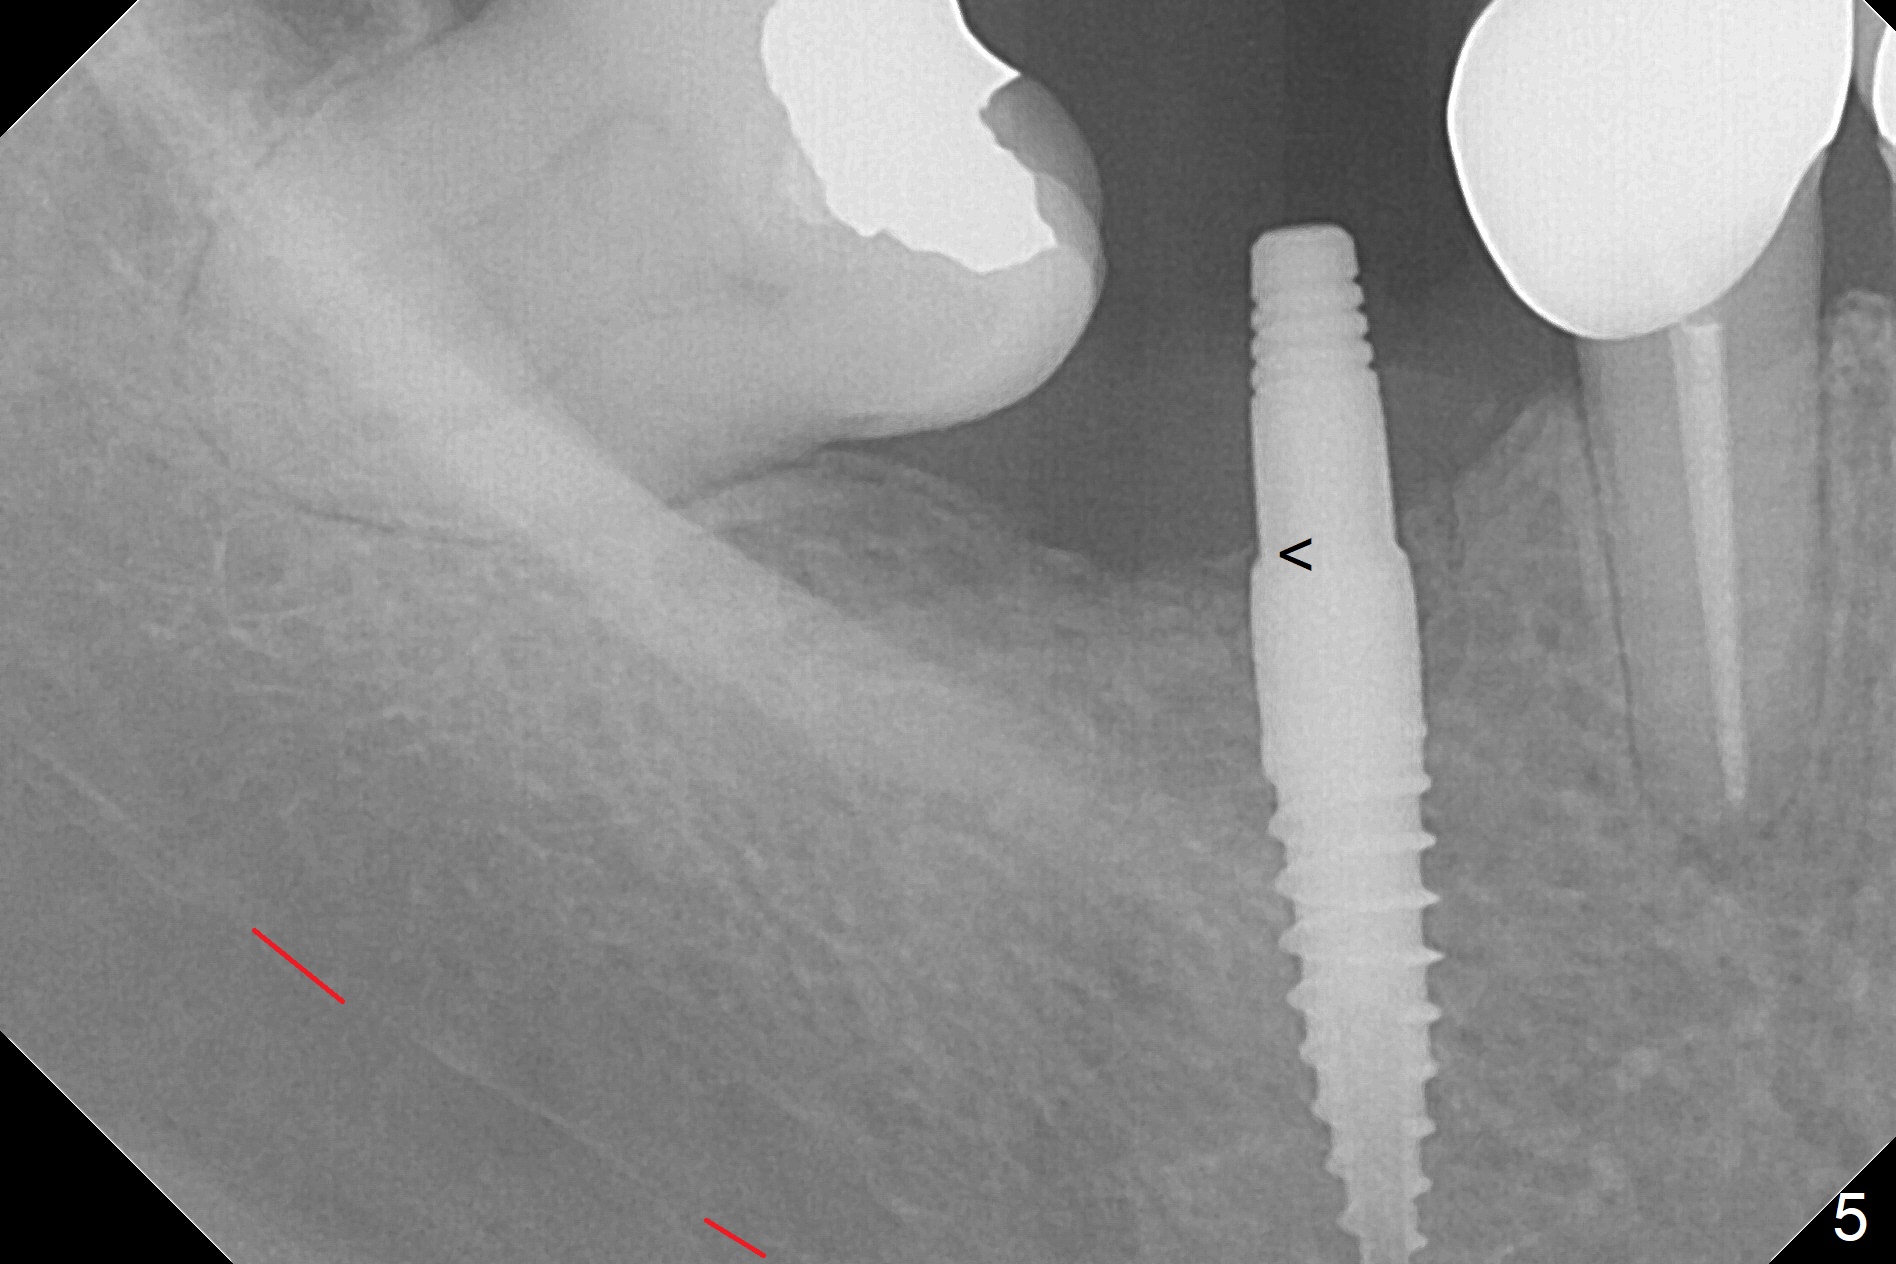

1-Piece Implant at Molar with Narrow Ridge

Incision reveals a narrow ridge and a narrow mesiodistal space at #30 (Fig.1). It seems that a 1-piece implant is indicated. Due to limited mouth opening, a 1.2 mm drill is unstable in place after use for 10 mm; instead a 1.5 mm drill is able to be inserted for 8 mm (Fig.2). A 3x10(2) mm 1-piece dummy implant is placed with 40 Ncm at an apparently acceptable level (Fig.3 >). Clinically a few threads are exposed buccally. When a definitive implant with the same dimension is inserted with 45 Ncm, it looks seated too deep (Fig.4,5). The latter is noted after suturing. The implant is backed up for a few turns so that the length of the abutment appears a little more reasonable. Introspectively, a 4 mm cuff should have been used after ridge reduction. Although there is no bone loss 4 months postop (Fig.6), the abutment margin (Fig.7 arrow) is subgingival (red dashed line: gingival margin). Diode laser is used for gingivectomy prior to impression. The bone density around the implant increases 11 months post cementation (Fig.8 *), probably related to recurrent #18 infection. The patient uses floss after meal.